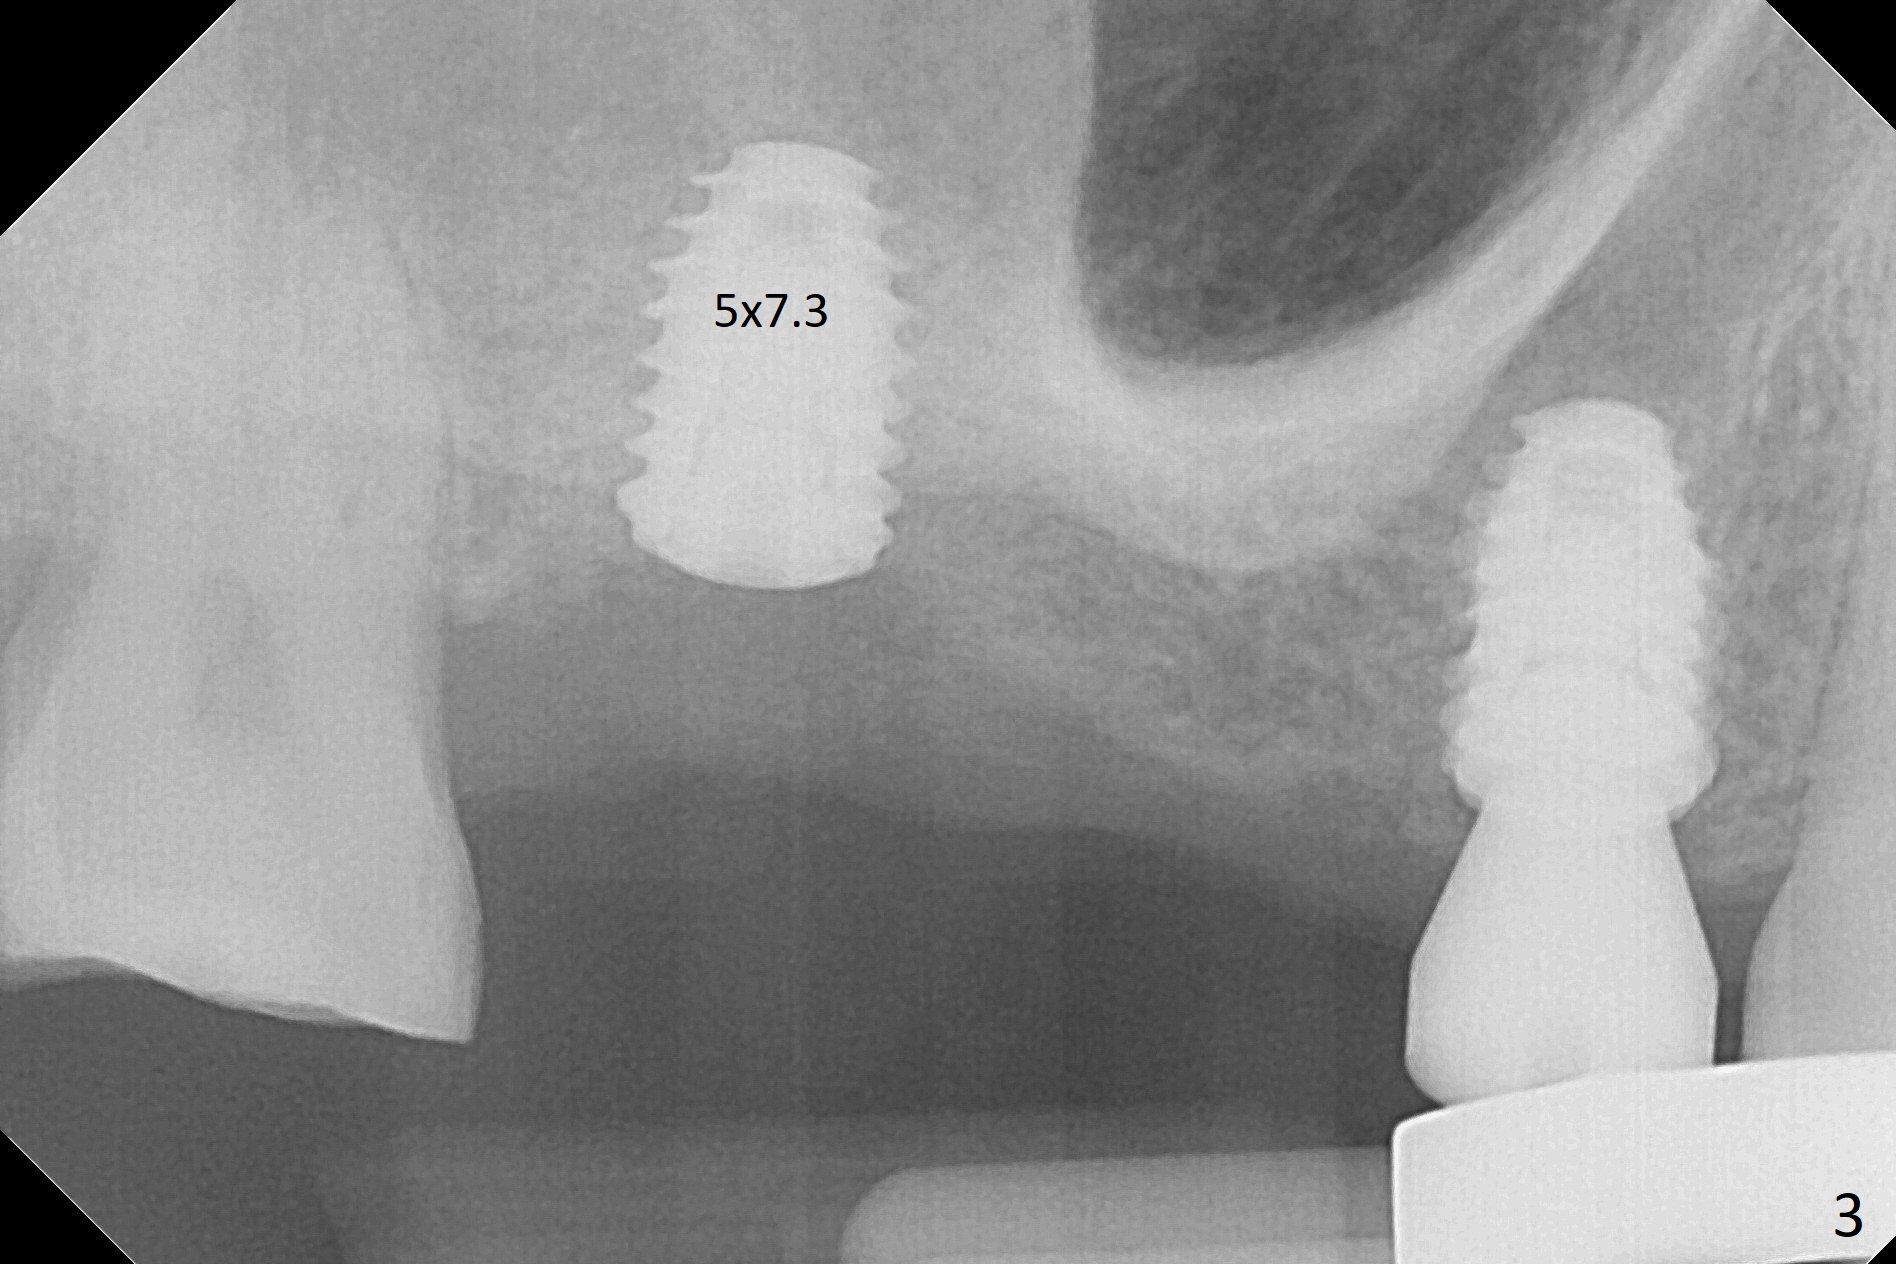

Eight months post socket preservation, the bone density at #2 feels low during osteotomy.  The site is underprep not only in depth, but also in diameter (4.0x7.3 mm with 10.5 mm offset), but a 5x7.3 mm implant is ~ 1 mm shy of the purposed depth.  Following 4.5x7.3 and 4.0x8.5 mm drills (without air leak), the implant reaches the depth, but with ~ 5 Ncm insertion torque (Fig.1).  Placement of the same sized implant at #4 (healed site) is smooth with satisfactory stability (~30 Ncm, Fig.2,3).  Ideally the site of #2 should have been prepared with sinus lift so that the apex of a longer implant would be engaged to the sinus floor for stability.  These two implants heal normally clinically and radiographically 1.5 months postop (Fig.4-6).  Bone surrounds the implant at #2 when it is uncovered 4 months postop (Fig.7).  The retainer at #4 looks short with large gingival embrasure (Fig.8 *) 6.5 months postop.  Finally the patient is ok with it because she does not like gingivectomy.  Provisional should have fabricated (Fig.9 light yellow curved lines) to create gingival scallops with secondary formation of papillae (arrows).